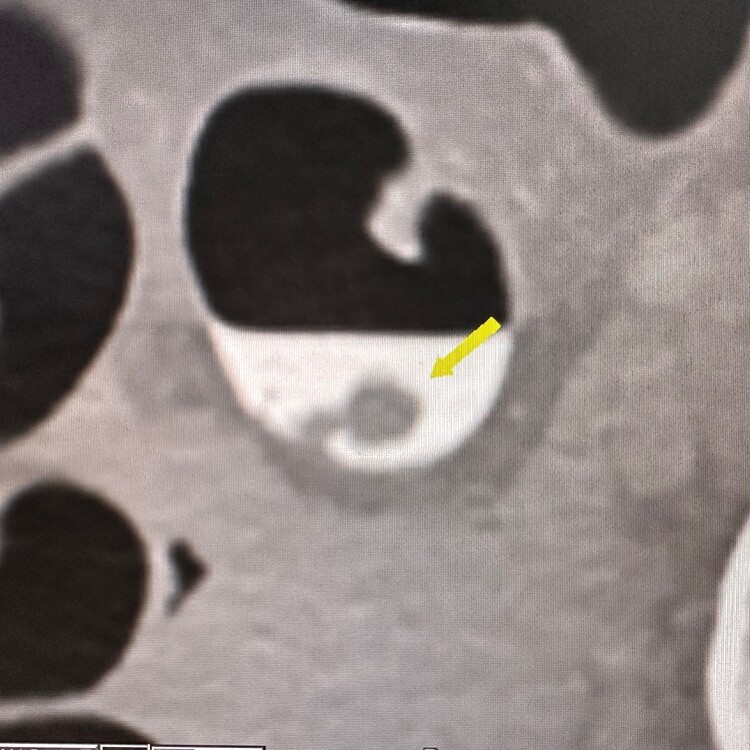

14mm diameter stalked polyp in patient with no symptoms and FIT test negative. CT colonography has identified the polyp using an endoluminal display

The source CT image display with the polyp surrounded by tagged ‘white’ fluid